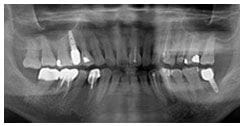

X 光片

術後X光片